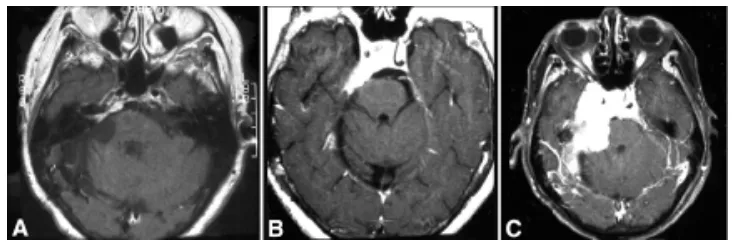

56岁女性患者于1981年接受右侧蝶岩斜区脑膜瘤切除术。1991年(患者66岁时)随访MRI显示内听道内侧及上方出现小型肿瘤复发(图1A)。患者接受伽玛刀治疗后,影像学随访保持稳定直至1999年,此时出现右侧面部感觉异常、面肌痉挛及进行性共济失调(图1B)。2001年随访影像学检查显示脑膜瘤在过去两年显著进展(图1C)。肿瘤累及右侧岩斜缘,延伸至右侧海绵窦及视神经管,并填充蝶鞍,向左侧海绵窦延伸。临床再评估显示症状进展:右侧面肌无力加重,第III、V、VI对颅神经右侧不全麻痹,伴发声及轻度构音障碍。患者最终接受经岩骨前入路显微镜下肿瘤切除。术中发现沿斜坡后方、垂体窝内及双侧海绵窦存在残留脑膜瘤,因部分肿瘤组织与脑干粘连紧密,切除范围受限。术后患者定期随访监测。